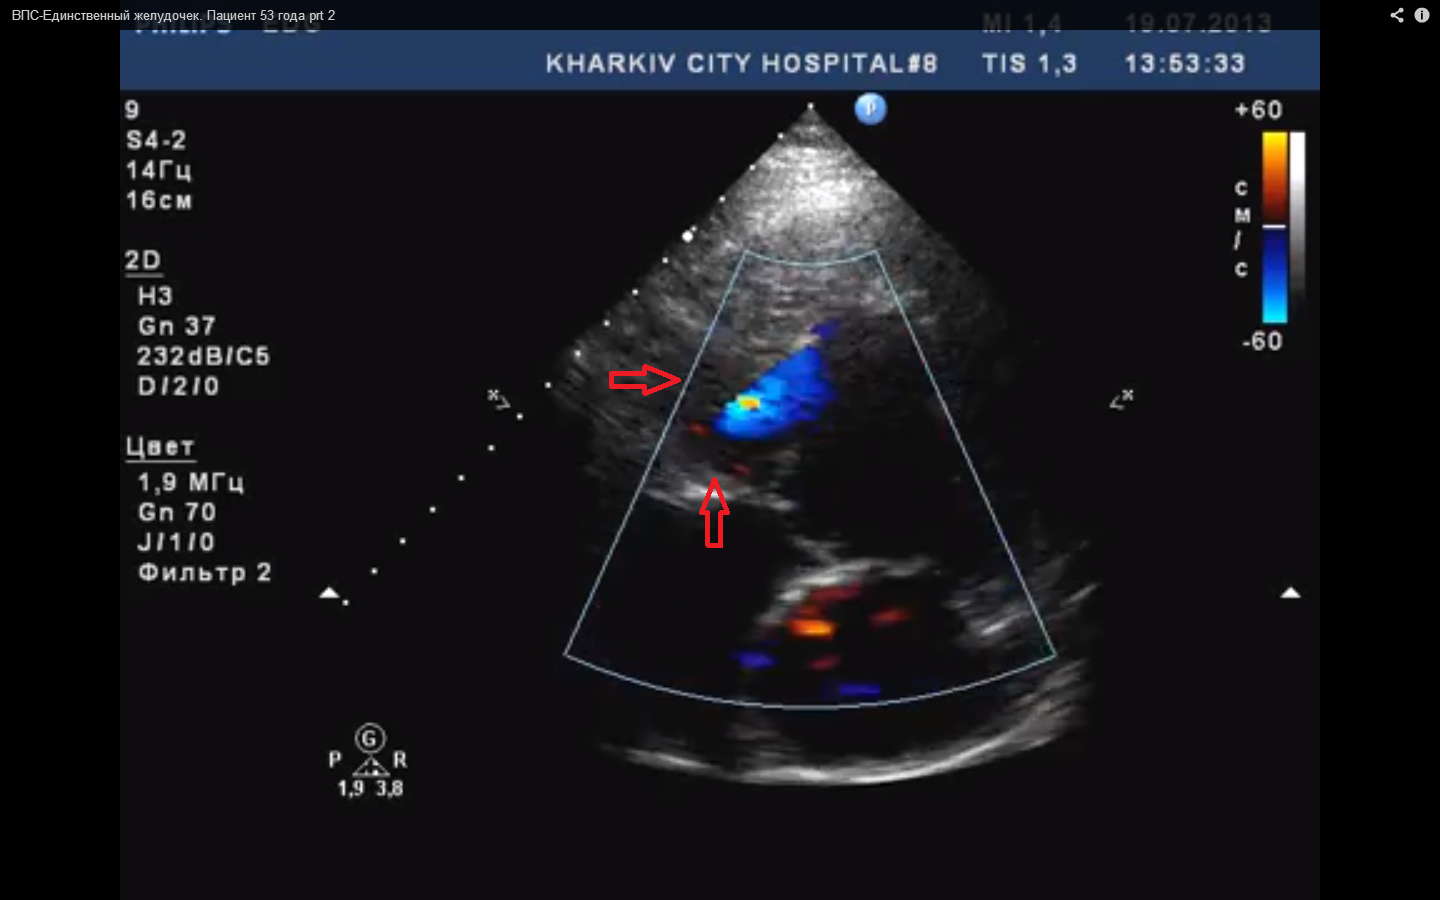

Поступил в клинику пациент 53 (!) года. Со слов пациента ВПС в детстве предлагали оперировать - отказались. Никаких документов нет. Когда- то якобы делали ЭХО-КС и озвучивали еще и транспозицию магистральных сосудов.

Доступ только апикальный. аорта не визуализируется. удается вывести только легочную артерию (по бифуркации ствола вывод- ЛА). Дилатация предсердий до 4.6см. отсутсвует МЖП, диаметр единственного желудочка 9.5 см. ТЗСЛЖ 1.0см. Высокая ЛГ. Для снятия вопроса по ТМС рекомендовано КТ.

ВПС: единственный желудочек.